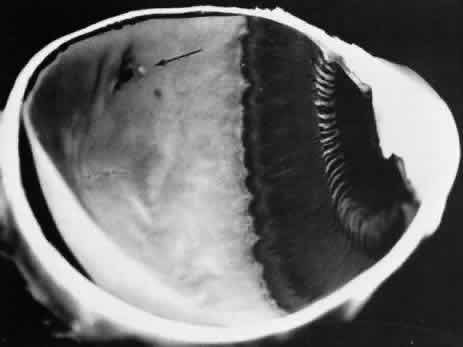

meridian (Fig. 9). The large dentate process and meridional fold are composed of excessive, disorganized, somewhat degenerated retinal tissue (Fig. 10).  Fig. 9. Meridional complex (arrow). Note its basic constituent, an atypical dentate process, which aligns

with and extends to an enlarged ciliary process. Complex also has a

meridional fold which extends along the dentate process and posteriorly

into the peripheral retina. Fig. 9. Meridional complex (arrow). Note its basic constituent, an atypical dentate process, which aligns

with and extends to an enlarged ciliary process. Complex also has a

meridional fold which extends along the dentate process and posteriorly

into the peripheral retina.